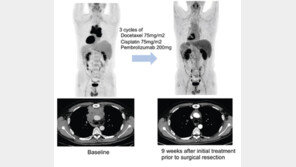

심장과 폐를 보호하는 가슴뼈(흉골)에는 나비 모양으로 생긴 ‘흉선’이라 불리는 기관이 있다. 사춘기 무렵까지 면역기관으로 역할을 하다 성인이 되면서 지방조직으로 바뀐다. 이곳에 생기는 암을 흉선상피종양이라고 부르는데, 면역항암제를 병용 투여할 경우 치료 효과가 있다는 임상 결과가 세계…